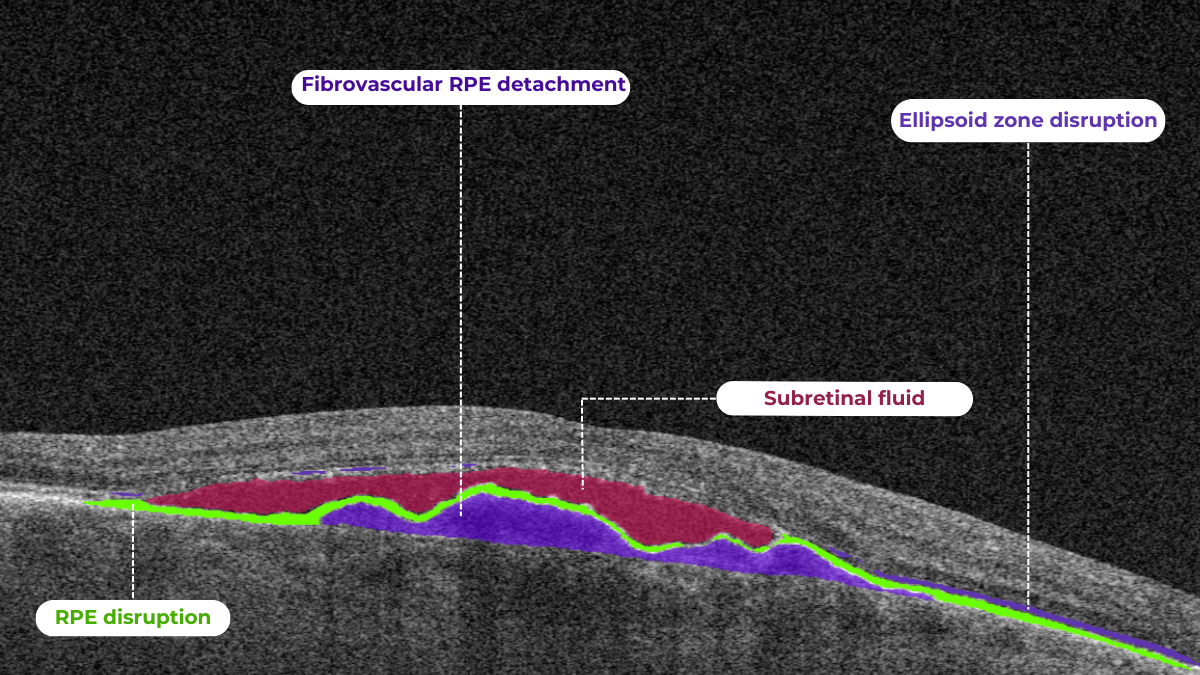

On OCT, diabetic retinopathy (DR) can appear as a combination of retinal structural damage, fluid accumulation, and microvascular changes that may not be visible on fundus photography.

Typical OCT findings in DR include:

• Photoreceptor damage – loss of outer retinal layers, especially the ellipsoid zone

• Intraretinal hyperreflective foci, hard exudates

• Microaneurysms – visible as small, round changes within the retina

• Retinal thickness changes and neuroepithelial layer atrophy

• Diabetic macular edema  – with intraretinal hyporeflective cystoid spaces and neuroepithelial swelling

• Subretinal fluid  – resulting from increased vascular permeability

• DRIL – disorganization of inner retinal layers, associated with poor prognosis

• Epiretinal membranes – potential precursors to retinal detachment

The main OCT biomarkers in DME include:

• Cystoid hyporeflective intraretinal spaces – usually in the inner nuclear layer (INL) or outer plexiform layer (OPL). Their number, size, and location correlate with edema severity. Large or confluent spaces may indicate chronicity and a worse prognosis.

• Subretinal fluid – accumulation between the neurosensory retina and retinal pigment epithelium. Often associated with a better visual prognosis, but requires close monitoring and consideration in anti-VEGF therapy.

• Central macular thickening – a key marker of treatment effectiveness and disease activity.